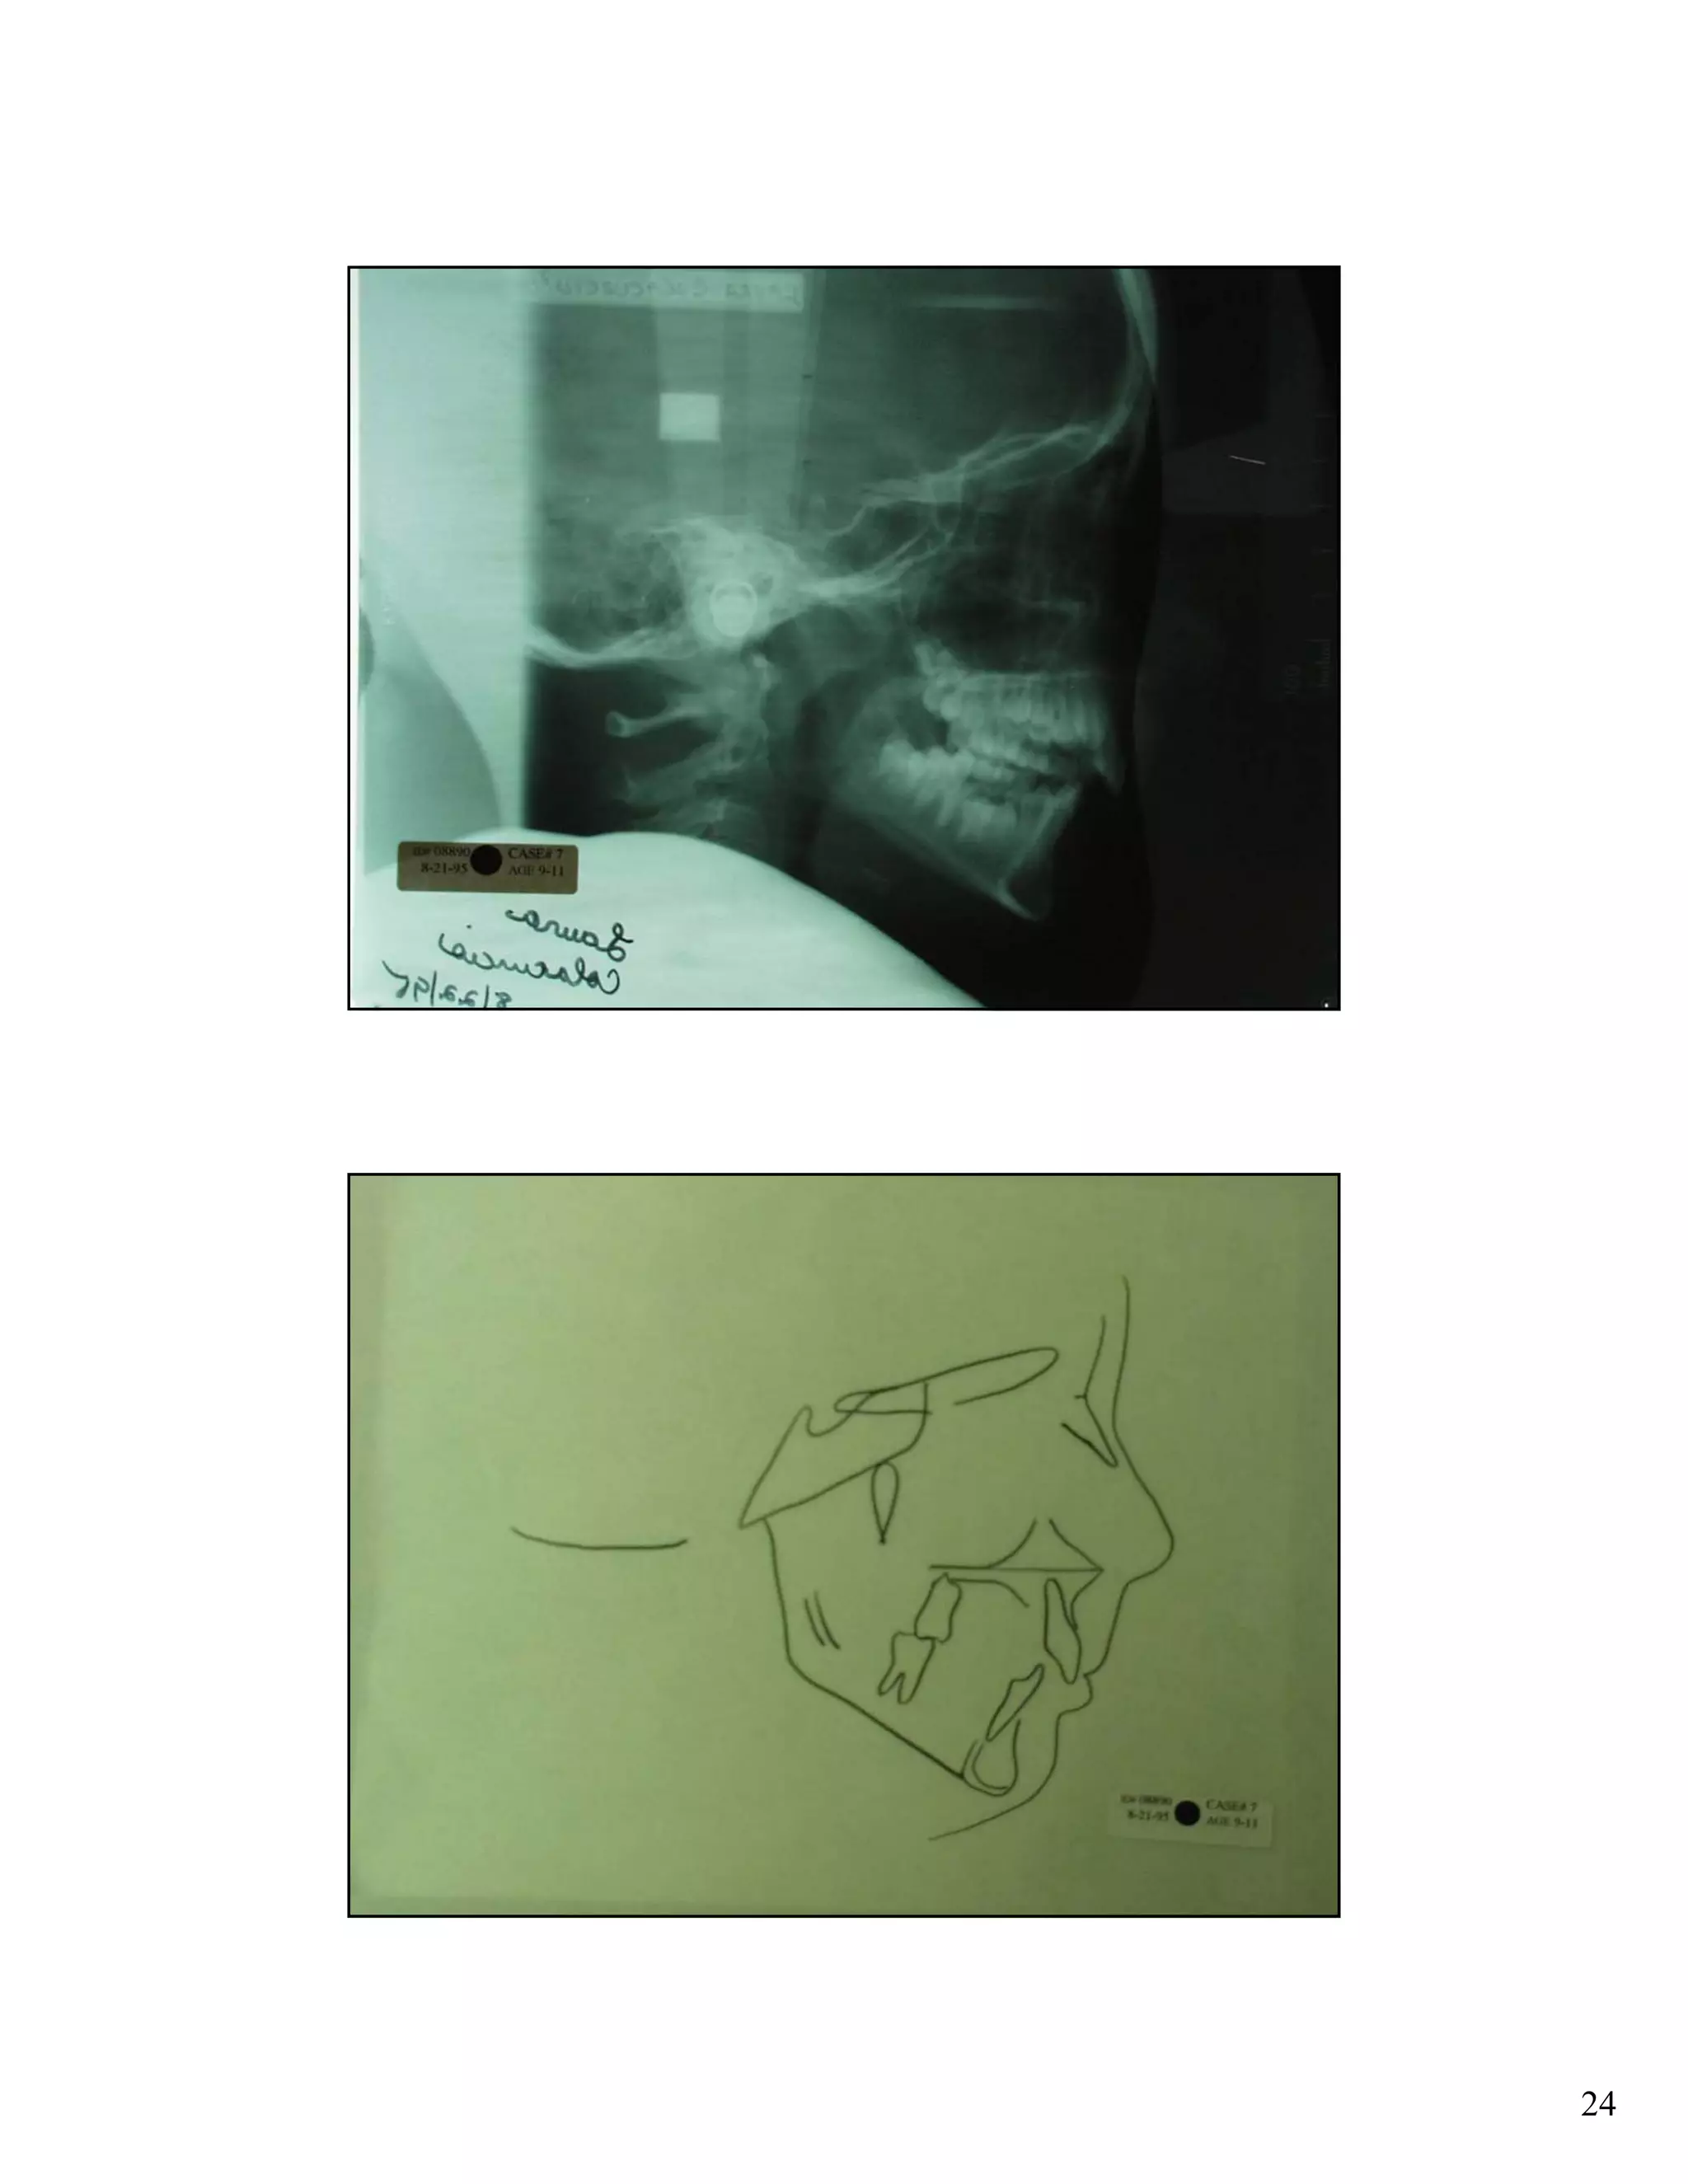

Cephalometric analysis uses x-rays of the skull to measure the growth and development of facial structures. Key indicators include the SN:GoGn angle measuring lower facial growth direction, the S-Go/N-Me ratio comparing posterior and anterior facial heights, and extension of the GoGn line to the occiput. These measurements help assess growth trends and plan orthodontic treatments.